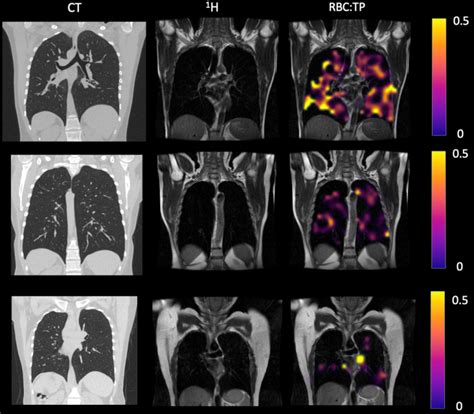

When it comes to spotting abnormal lung imaging findings , doctors have a whole arsenal of cool technologies at their disposal. Each tool offers a unique perspective on your lungs, like different lenses providing varied levels of detail. Let’s chat about the main players and how they help diagnose those abnormal findings . First up, the old reliable, the Chest X-ray (CXR) . This is often the first line of investigation, like the initial scout. It’s quick, relatively inexpensive, and uses a small amount of radiation to provide a two-dimensional image of your chest. A CXR can effectively show large abnormal findings like significant pneumonia , pleural effusions , or big masses . It’s great for screening and for monitoring conditions like heart failure or certain infections. However, its main limitation is its lack of detail; smaller nodules or complex structures might be obscured by overlying bones or tissues. Think of it as a broad overview – good for big picture stuff, but not for fine details. For that, we step up to the Computed Tomography (CT Scan) . This is the real MVP for detailed lung imaging. A CT scan uses X-rays from multiple angles to create highly detailed, cross-sectional (slice-by-slice) images of your lungs and surrounding structures. It’s phenomenal for characterizing abnormal lung imaging findings such as pulmonary nodules (assessing their size, shape, margins, and density with much greater precision), interstitial lung diseases , bronchiectasis , and complex masses . We even have High-Resolution CT (HRCT) specifically designed for incredibly fine detail of the lung parenchyma, which is essential for diagnosing conditions like pulmonary fibrosis . Sometimes, a contrast dye is used to highlight blood vessels or certain tissues, especially when looking for pulmonary embolisms or assessing tumor vascularity. A CT scan provides a three-dimensional understanding, which is invaluable for intricate diagnoses. Then there’s Magnetic Resonance Imaging (MRI) . While not as commonly used for the lung parenchyma itself due to movement artifacts from breathing and the lung’s air content, MRI excels in specific situations. It’s particularly good for imaging the mediastinum (the space between the lungs containing the heart, major blood vessels, and trachea), the chest wall , and for assessing vascular invasion by tumors. MRI doesn’t use radiation, which is a plus, and it provides excellent soft tissue contrast, making it useful for evaluating lymph nodes or masses near the diaphragm. Lastly, we have Positron Emission Tomography-Computed Tomography (PET-CT) . This is a powerful hybrid imaging technique, primarily used in oncology. It combines the anatomical detail of a CT scan with the functional information of a PET scan. A PET scan involves injecting a small amount of radioactive sugar (FDG) into your bloodstream. Cancer cells, being very metabolically active, tend to absorb more of this sugar. The PET scan then lights up these areas, showing where there’s increased metabolic activity. So, a PET-CT can help determine if an abnormal lung imaging finding (like a nodule or mass) is likely benign or malignant , stage cancers, and detect recurrence. It provides a unique insight into the biological activity of the findings, complementing the anatomical information from the CT. Each of these techniques plays a vital role in identifying, characterizing, and monitoring abnormal lung imaging findings , with doctors carefully selecting the most appropriate one based on the patient’s symptoms, risk factors, and initial findings. It’s a dynamic interplay of different technologies, all aimed at getting you the clearest picture possible of your lung health.